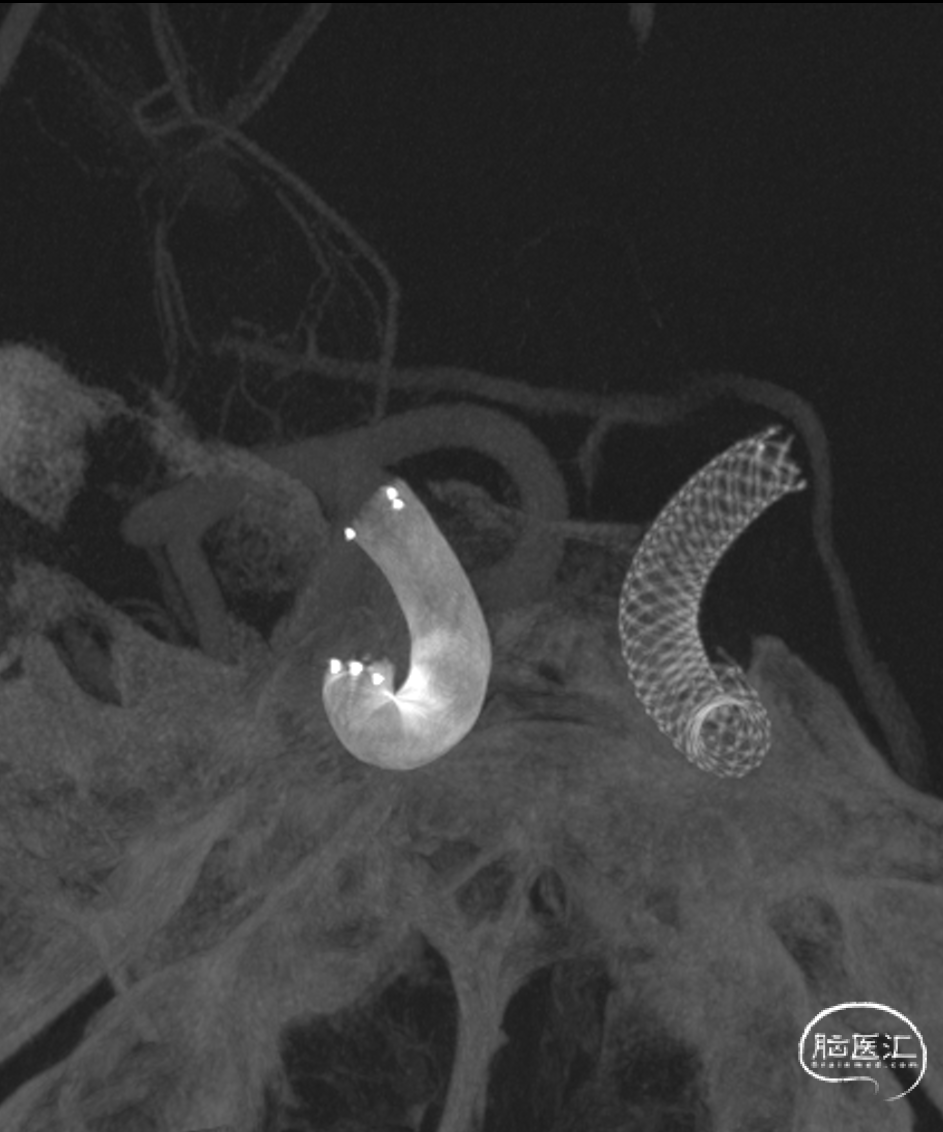

通桥麒麟™血流导向密网支架释放模拟图。

迂曲段通桥麒麟™血流导向密网支架释放过程。

通桥麒麟™血流导向密网支架成功释放。

通桥麒麟™血流导向密网支架完全释放,术后造影。

术后血管造影见动脉瘤仍有显影,瘤腔内造影剂滞留,支架展开,贴壁良好,载瘤血管血流通畅,手术顺利。